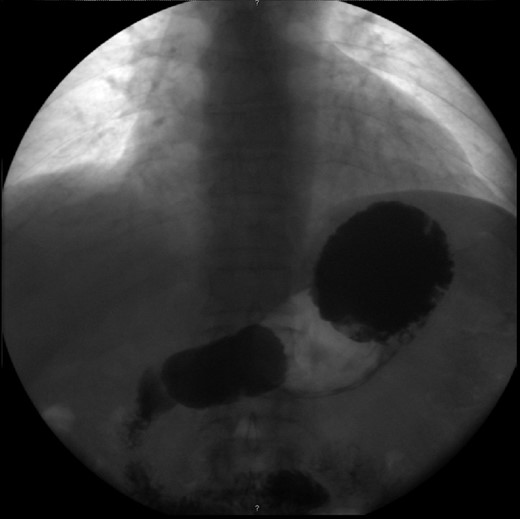

The patient’s leucocyte count and serum amylase presented mildly elevated. Chest radiograph revealed an elevated left hemi-diaphragm. Abdominal radiographs demonstrated a spherical stomach, presupposing an upward position of the pylorus (Fig. 1).

Abdominal radiograph, demonstrating a spherical stomach, presupposing an upward position of the pylorus.